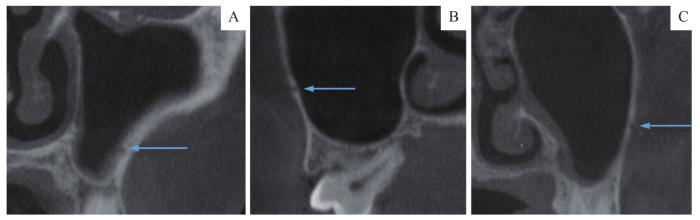

图3

MSA走形位置变异

Note:A.The MSA was located at the bottom of maxillary sinus. B. The MSA was located in the root apical of molars. C. The MSA was located in the alveolar bone 4.14 mm from maxillary sinus floor.

Fig 3

Variability of the MSA position